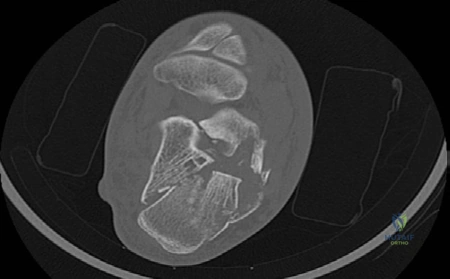

Figure 8.5 CT scan axial view left foot demonstrating calcaneal fracture.

conditions such as diabetes and peripheral vascular disease as well as smoking and occupation. EXAMINER : Okay, this is the CT scan you requested, what can you see and what would you do next? (Figure 8.5.) CANDIDATE : This CT scan section in axial view shows shorting of the calcaneus, varus deformity with a comminuted displaced fracture. There is a large sustentacular fragment, depressed middle fragment and blow-out of lateral wall. It also shows considerable heel widening.